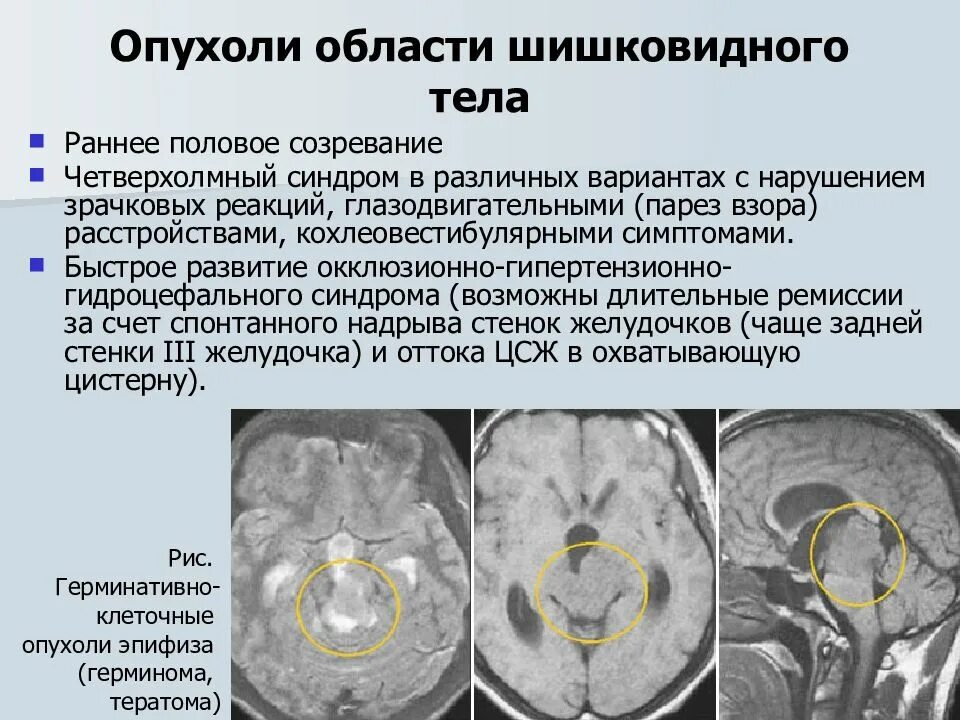

Феохромоцитома диагно. Феохромоцитома методы диагностики. Феохромоцитома локализация. Исследования при феохромоцитоме. Опухоль шишковидного тела. Опухоль шишковидного тела в головном мозге. Пинеалома опухоль шишковидной. Опухоль шишковидной железы симптомы.

Опухоль шишковидного тела. Опухоль шишковидного тела в головном мозге. Пинеалома опухоль шишковидной. Опухоль шишковидной железы симптомы. Глиома внутримозговая кт. Метастатические опухоли мозга.